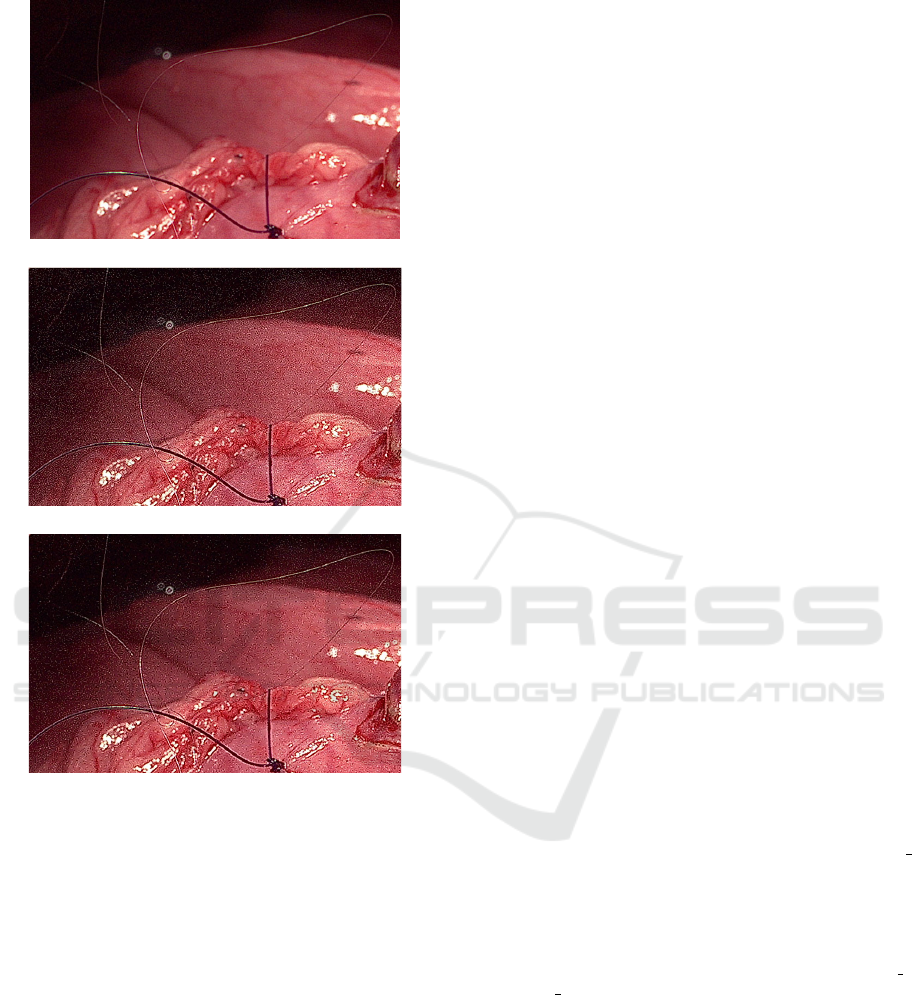

cessing in this study. In the laparoscopic surgery, a

0.02 mm diameter thread is used and is only visible

when an 8K endoscope with fine focus is used. How-